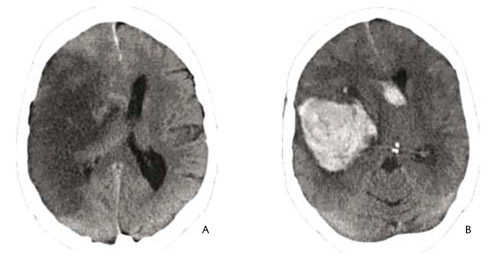

op de onderstaande afbeelding zijn 2 CT scans zichtbaar:

Links is een scan zichtbaar van een herseninfarct, door afsluiting van een slagader valt een deel van de hersenen uit door gebrek aan zuurstofrijk bloed. Het bloedarme gedeelte tekent zich donkergrijs af.

Rechts is een scan zichtbaar van een hersenbloeding, Door een scheur in de slagaderwand is bloed in het hersenweefsel terecht gekomen. Het bloed in het hersenweefsel tekent zich lichtgrijs af